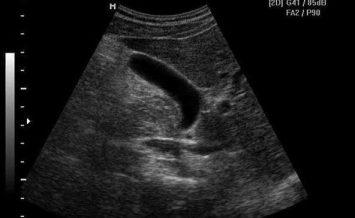

Патология выражена признаками диспепсии, не имеет стандартного очага. Характерные перегибы желчного пузыря провоцируют перетяжение тела с последующим риском его разрыва. Боль имеет неопределенную локализацию, необходимо проведение УЗИ для определения пораженного участка. Если здоровый орган имеет вид мешка, то пораженный – приобретает очертания бумеранга, песочных часов, грушевидную форму. Сначала болевой синдром выражен слабо, но со временем становится интенсивным, и действие анальгетиков уже не способно продлить период ремиссии.

Диагностика загиба

Диагностировать загиб несложно. Наиболее информативным методом диагностики патологии является ультразвуковое исследование. Оно позволяет не только выявить патологию, но и определить функциональное состояние органа, точную локализацию загиба, а также оценить анатомические особенности стенок, шейки, тела.

Определить причину патологии сложнее. Для дифференциации врожденного заболевания от приобретенного ультразвуковое исследование желчного проводится дважды: на голодный желудок и после употребления яичных желтков, которые вызывают повышенное выделение желчи. Когда перегиб пузыря является врожденной патологией, деформация органа остается без изменений.

В рамках инструментальной диагностики назначают ультразвуковое исследование.

- Обследование проводят натощак.

- Обследование проводят спустя полчаса после приема медикаментов, активизирующих синтез желчи, или продуктов, обладающих подобным действием. Диагност может определить тип патологии – при фиксированной деформации изменения отсутствуют, в случае приобретенного загиба орган уменьшится.

Степень перегиба органа, депонирующего желчь, определяет вероятность развития его дисфункции, возможных сопровождающих заболеваний, а также скорость наступления этих последствий и их динамику. Встречаются изгибы различной конфигурации, единичные, множественные. В результате желчный пузырь на мониторе аппарата УЗИ проявляется удивительными формами, например:

Известно, что в группе обратившихся за медицинской помощью в связи с болезнями билиарной системы перегиб диагностируется методом УЗИ примерно у 30% пациентов.